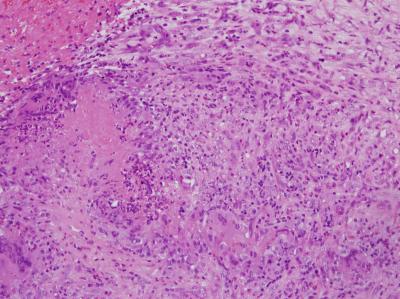

Figure 1: TURP sample showed granulomatous inflammation accompanied by central necrosis